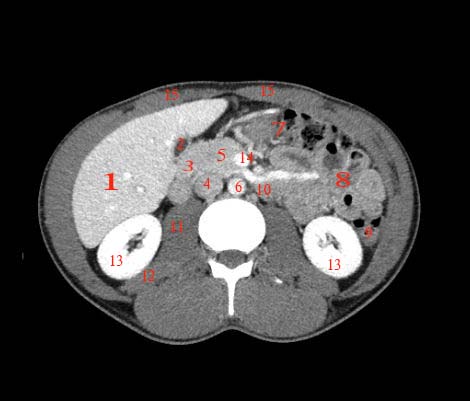

Abdomen axial IQ Test